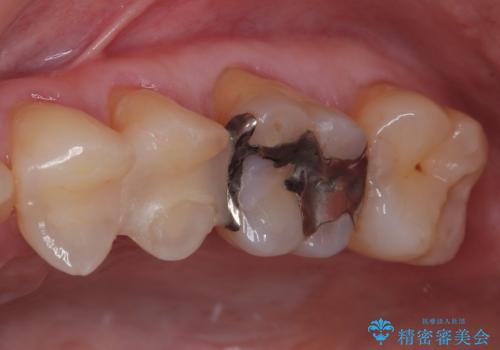

- 銀歯が取れたとのことで来院された患者様です。患者様の歯をあまり削りたくないというご希望に添い、セラミックインレーにて治療を行うこととなりました。

拡大鏡視野下で、保険のプラスチック、虫歯の除去を行い、セラミックインレーに適した形に整えました。